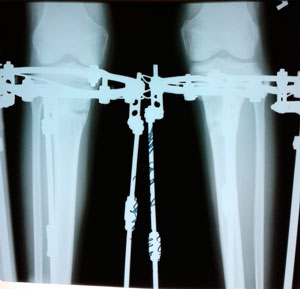

Исходник - 32 года.

Дата операции 28.01.2020

на фиксации